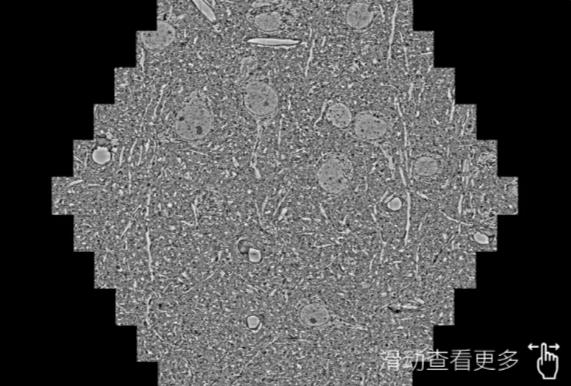

鼠脑切片。左图使用柳州蔡司柳州扫描电镜MultiSEM706对165μmx143pm面积区域成像,耗时仅需1.5秒。右图为鼠脑切片中30μm区域放大效果。样品由芝加哥大学B.Kasthuri提供。

使用蔡司高速柳州扫描电镜MultiSEM对1mm²人脑皮层组织进行高分辨成像,并对其中的各种细胞结构进行三维重构分析。左图展示了2x3mm²组织平面中锥体神经元的三维重构效果。右图显示了局部体积神经元三维重构。图像由哈佛大学chtman实验室提供,渲染图由D. Berger 制作。